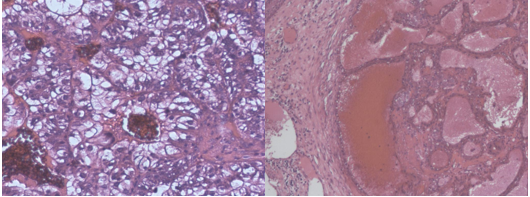

The tissue was sent for histopathological examination, which confirmed that the lesion was a metastatic carcinomatous neoplasm with clear cells alternating with granular cytoplasmic cells and very rich vascularization (figures 8 and 9).